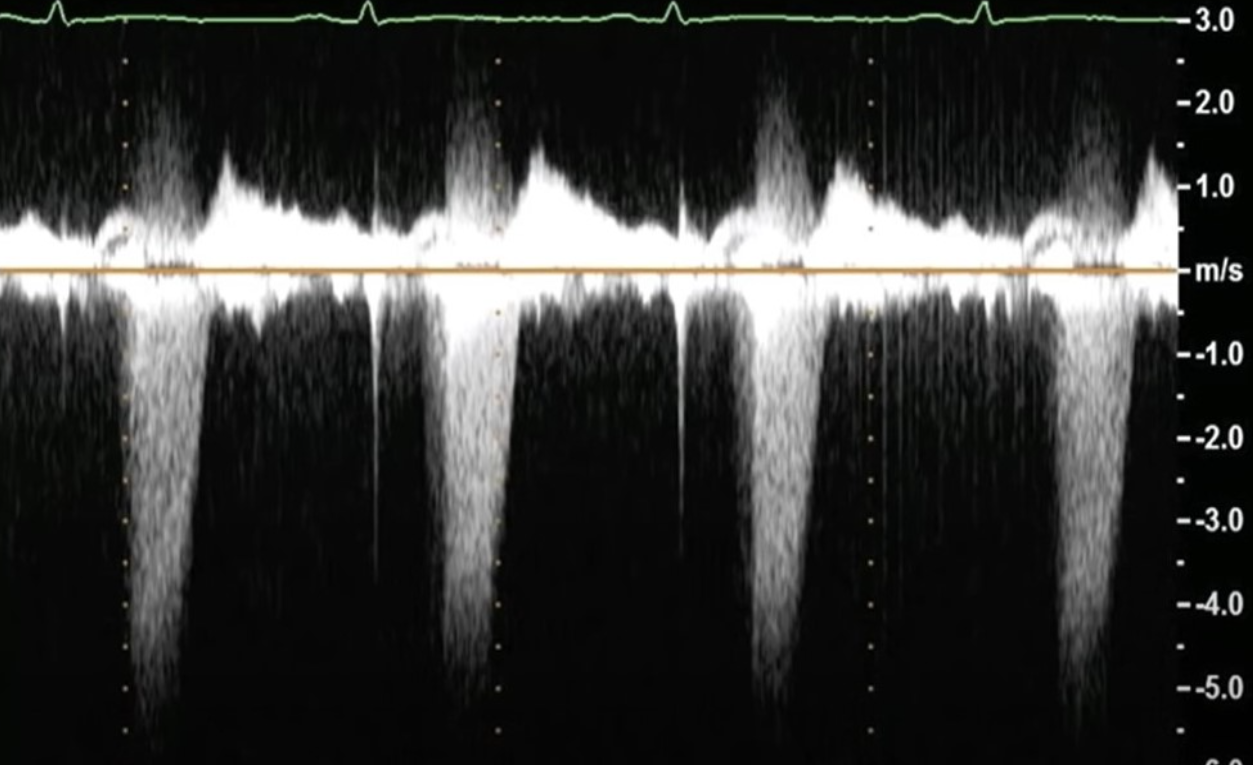

Note the width and length of the jet

Severe TR